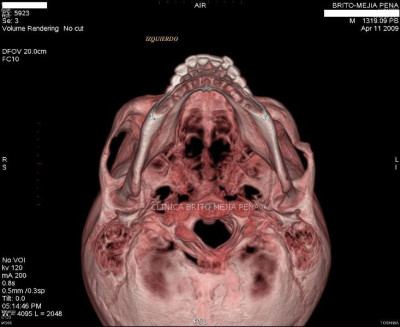

Detalle óseo